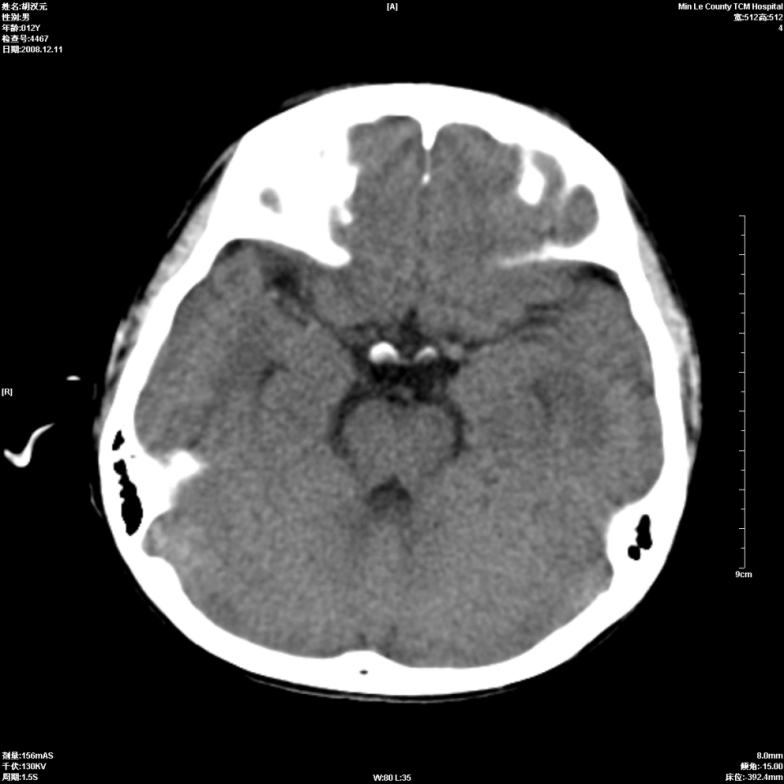

标题: PED1681:头疼发热约一周 [打印本页]

标题: PED1681:头疼发热约一周

颅脑未见确切异常。必要时进一步检查,如mri、脑脊液检查。

两侧顶部近灰质处白质密度降低,是否炎性改变

颅脑ct轴位平扫颅内未见明确异常;建议必要时复查或行进一步检查。

两侧顶部近灰质处白质密度降低,建议mri